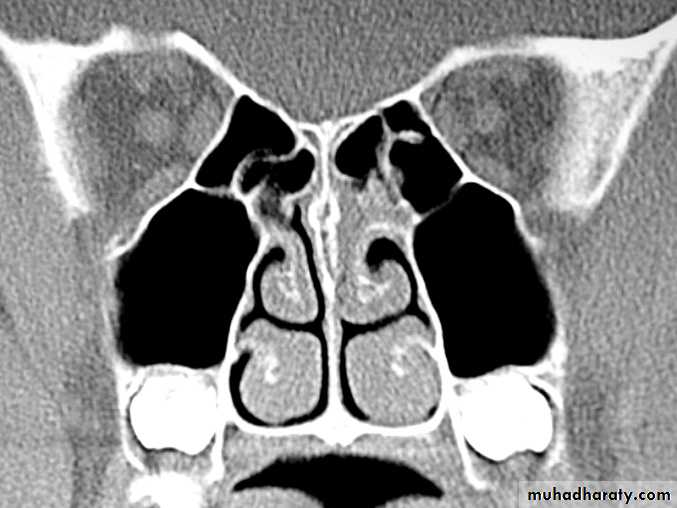

• b)Hypertrophic rhinitis

• Aetiology• The condition represent an advanced stage of simple chronic rhinitis , in which permanent hypertrophic changes have followed . the causes are similar , but it is frequently seen also in patient who have used topical decongestant in large quantities and /or for long periods ( rhinitis medicamentosa )

• Pathology

• .permanent hypertrophic changes accompany the inflammatory oedema and cellular infiltration in all the constituent parts of the mucosa i.e. stroma , glands , blood vessels , and lymphatic tissue . the epithelium loses clilia and shows a tendency to squamous metaplasia . the mucosa becomes thick and nodular , especially at the extremities and free border of the the occupy the posterior choana . fibrosis can cause venous and lymphatic obstruction . if the resulting passive edema occurs in the situation where the mucosal stroma is loose , polypi form . nasal polyposis , however , usually indicate an allergic or vasomotor origin of the rhinitis , in which the polyposis results from increases capillary permeability• Clinical features

• Similar to those of simple chronic rhinitis but are unremitting in character pitting of the firm mucosa with a probe and shrinkage with cocaine are less marked than in simple chronic rhinitis• Treatment

• As for simple chronic rhinitis , with the addition of limited reduction of the hypertrophied inferior turbinate and removal of any polypi . topical decongestant preparation must be discouraged or discontinued . reduction is achieved by :• . electrocoagualtion : by SMD or linear cauterization by galvanocautery